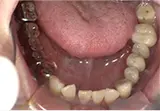

| 年齢/性別 | 50代女性 |

| 主訴 | 左下奥歯に痛みがある、全体的に治したい |

| 治療内容 | 全体的に歯周病やむし歯、根の治療を行い、仮歯を使用して咬合治療を実施。右下2本、左下1本の計3本を抜歯し、その後、右下に2本、左下に2本の計4本のインプラントを埋入しました。 |

| 治療期間 | 8か月 |

| 費用 | 2,106,500円税込 |

| リスク・副作用 | 炎症反応によって術後に腫れが生じることがあります。その程度は、手術の範囲や方法によって異なりますが、多くの場合、時間の経過とともに徐々に治まります。 ごく稀に、下顎奥歯の外科手術後に、唇や顎に痺れを感じることがあります。 |